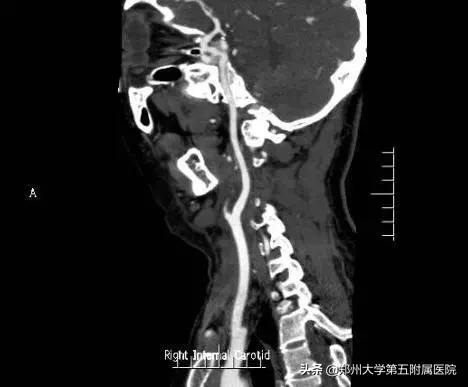

手术后,病人经过血管外科团队的精细护理治疗,现已顺利康复出院。后期复查CTA颈动脉通畅良好,瘤体未再显影。

▲ 术后复查CTA颈动脉光滑,周围无占位